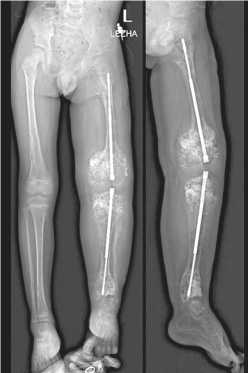

Период фиксации пациент провел по месту жительства. Контроль состояния пациента осуществлялся дистанционно, по переписке, с выполнением рентгенограмм каждые 30 дней. Костное сращение было констатировано по рентгенограммам через 30 дней фиксации (рис. 6). Однако явиться для снятия аппарата, учитывая отдаленное место проживания от Центра Илизарова, пациент смог лишь спустя определенный период.

Демонтаж аппарата произведен под общей анестезией, титановые телескопические стержни оставлены in situ (рис. 7). На рентгенограммах после снятия отмечена корректная позиция телескопических стержней, адекватное удлинению их расхождение и сохранение фиксации резьбовых частей в эпифизах и апофизе большого вертела. Наложена дисциплинирующая гипсовая лонгета на 10 дней. Вертика-лизация с нагрузкой на конечность была разрешена на первый день после операции.

Рис. 6. Рентгенограммы нижней конечности, 30 дней периода фиксации

Рис. 7. Рентгенограммы после демонтажа АВФ